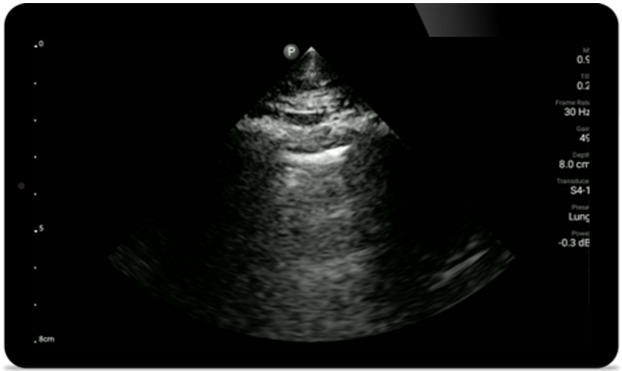

Lumify S4-1 broadband phased array transducer

• 4 to 1 MHz extended operating frequency range

• 2D, color Doppler, M-mode, advanced XRES and multivariate harmonic imaging

• High-resolution imaging for abdominal and cardiac applications: Cardiac, OB/GYN, Lung, Abdomen and FAST imaging preset optimizations